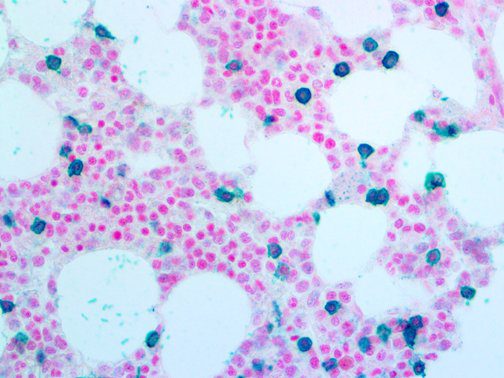

Clinical and laboratory manifestations of HLH include fever, enlarged liver and/or spleen, neurologic dysfunction, coagulopathy, liver dysfunction, cytopenias (i.e., low levels of erythrocytes, leukocytes, and/or platelets), hypertriglyceridemia, hyperferritinemia, hemophagocytosis, and eventually diminished NK cell activity as the immune system becomes progressively paralyzed. HLH can be familial (primary HLH) or secondary to another disease process (sHLH), such as rheumatic disease, in which it is referred to as macrophage activation syndrome (MAS, characterized by elevated ferritin).